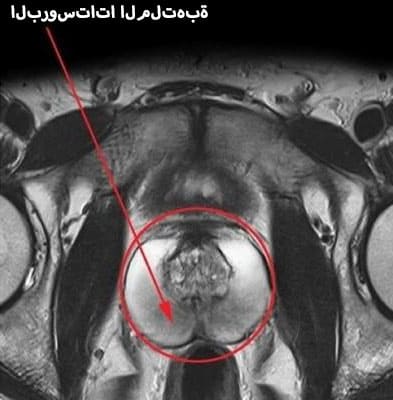

التهاب البروستات هو التهاب في غدة البروستاتا. أول خطر للإصابة بالتهاب البروستات هو أن هذا المرض، إذا لم تنتبه له، بعد 3 أشهر يمكن أن يتحول إلى شكل مزمن. وهذا يعني أن علامات التهاب البروستاتا يمكن أن تطارد الرجل طوال حياته وستزداد صحته سوءًا كل شهر

البروستاتا الطبيعية والملتهبة